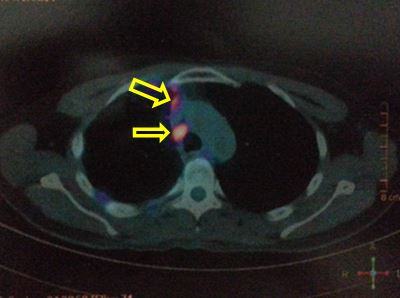

Hình ảnh PET/CT sau 3 đợt điều trị duy trì với Pemetrexed: các khối di căn và hạch không phát triển, max SUV có xu hướng giảm.

Nhiều nốt mờ dải rác phổi phải, màng phổi, max SUV = 4,25. Hạch cạnh khí quản 1,5 cm, max SUV = 4,93 (đầu mũi tên đỏ)

Hình ảnh PET/CT sau 3 đợt điều trị duy trì với Pemetrexed: các khối di căn và hạch không phát triển, max SUV có xu hướng giảm.Hình ảnh PET/CT sau 8 đợt hóa chất: nhiều nốt mờ dải rác phổi phải, màng phổi, max SUV = 4,7. Hạch cạnh khí quản 1,5 cm, max SUV = 6,4